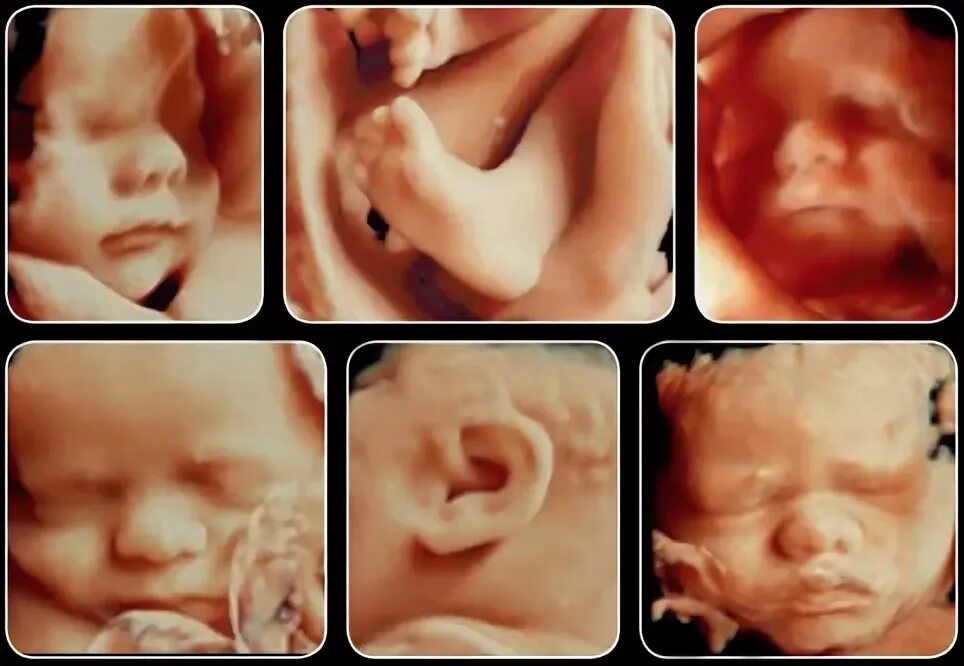

На каком сроке делать 3д